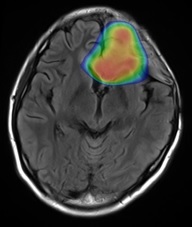

脳腫瘍

脳腫瘍には頭蓋内から発生した原発性脳腫瘍と、他の部位のがんが脳に転移した転移性脳腫瘍に分けられます。原発性脳腫瘍には悪性神経膠腫(グリオブラストーマ)などの悪性脳腫瘍と、髄膜種や聴神経腫瘍などの良性脳腫瘍があります。

腫瘍の種類、位置、大きさや腫瘍による症状、治療目的により放射線治療単独で治療したり、手術や薬物療法を組み合わせた放射線治療をしたりします。

照射線量は20~60Gy(グレイ)、照射期間は1~6週間程度です。

髄膜腫。内頸動脈を巻き込み脳幹を圧迫している。

放射線治療で増大を抑止し症状が出現するのを予防する。